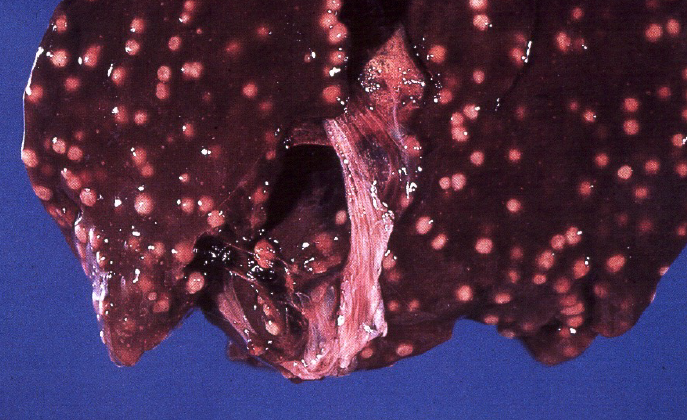

Etiology?

Mycobacterium tuberculosis (chronic)

T/F: This is the classic presentation of a liver infected with M**ycoplasma spp.

FALSE

Liver with Mycobacteriosis